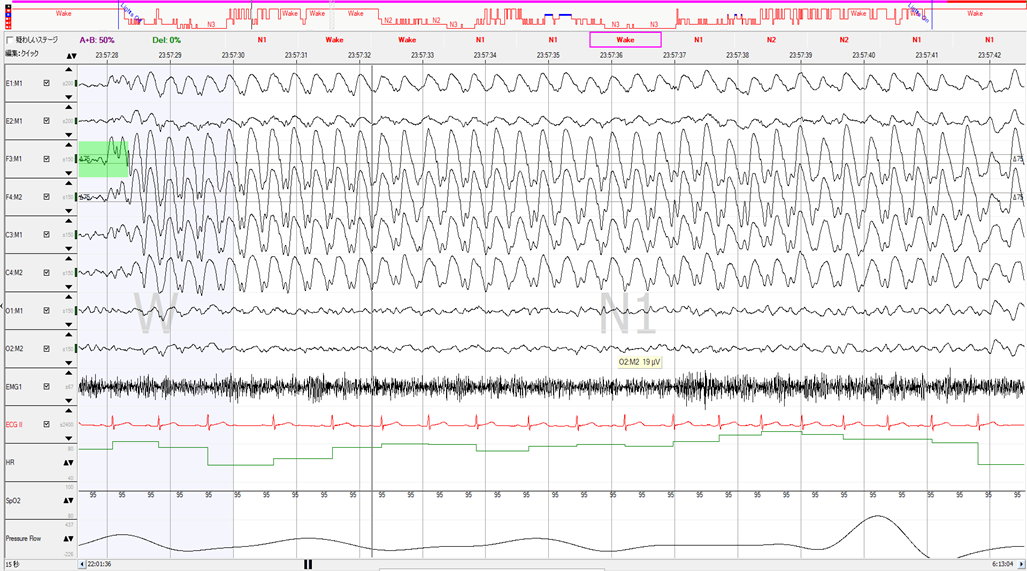

YUMINO'S コラム ゆみのPSGケースカンファ 学会・研究会 主要講演歴 著書出版歴 臨床研究 その他の活動 ゆみのPSGケースカンファ 2026年05月08日 記録前半は閉塞性呼吸イベントが主体で朝方CSR様の周期性呼吸を認めた症例 2026年05月01日 記録前半は閉塞性呼吸イベントが主体で朝方CSR様の周期性呼吸を認めた症例 2026年04月24日 超重症OSA症例の無呼吸と低呼吸 2026年04月14日 やせ型・若年者 でも重症のOSA症例 2026年04月10日 側臥位の就寝時間が長かったにも関わらず、重症の結果だったOSA症例 2026年04月03日 ノンレム睡眠側臥位の安定呼吸時の持続的なSpO2低下 2026年03月27日 CPAPタイトレーションで中枢性無呼吸が残存した症例 2026年03月13日 簡易検査結果と乖離して、大きく軽症化した症例 2026年03月06日 低振幅脳波で入眠判定が困難だったOSA症例 2026年02月27日 側臥位でも呼吸イベントが抑制されない重症OSAと徐波群発 1 2 3 4 5 年別 2026年 2025年 2024年 カテゴリー別